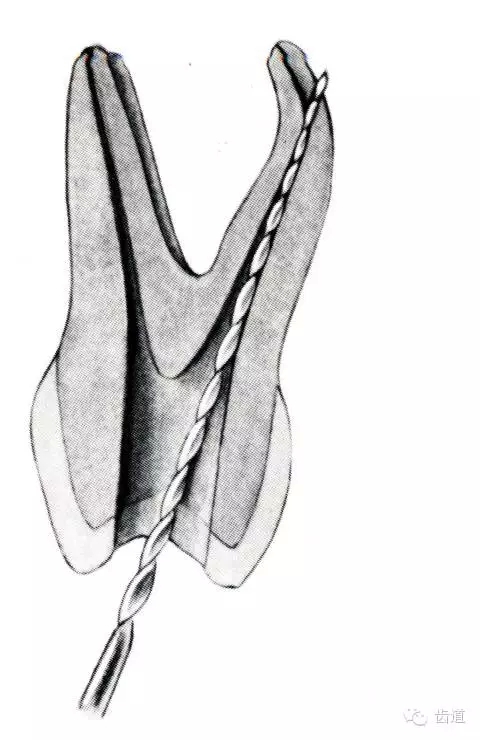

根管壁穿孔多在根管彎曲處。

(4)根管壁形成臺(tái)階:先換小號(hào)銼去除臺(tái)階,再順序擴(kuò)挫。如根管壁穿孔,找到主根管進(jìn)行預(yù)備后,主根管及側(cè)穿道同時(shí)充填。在根尖1/3或根尖彎曲處側(cè)穿,根充后,配合根尖手術(shù)——根切+倒充填。

3.根管清理和成形以及做冠樁預(yù)備過(guò)程中,過(guò)多的磨除根管壁,削弱了牙根強(qiáng)度。

4.用牙膠做根管充填時(shí),側(cè)向或垂直壓力過(guò)大,均可造成牙根縱折。